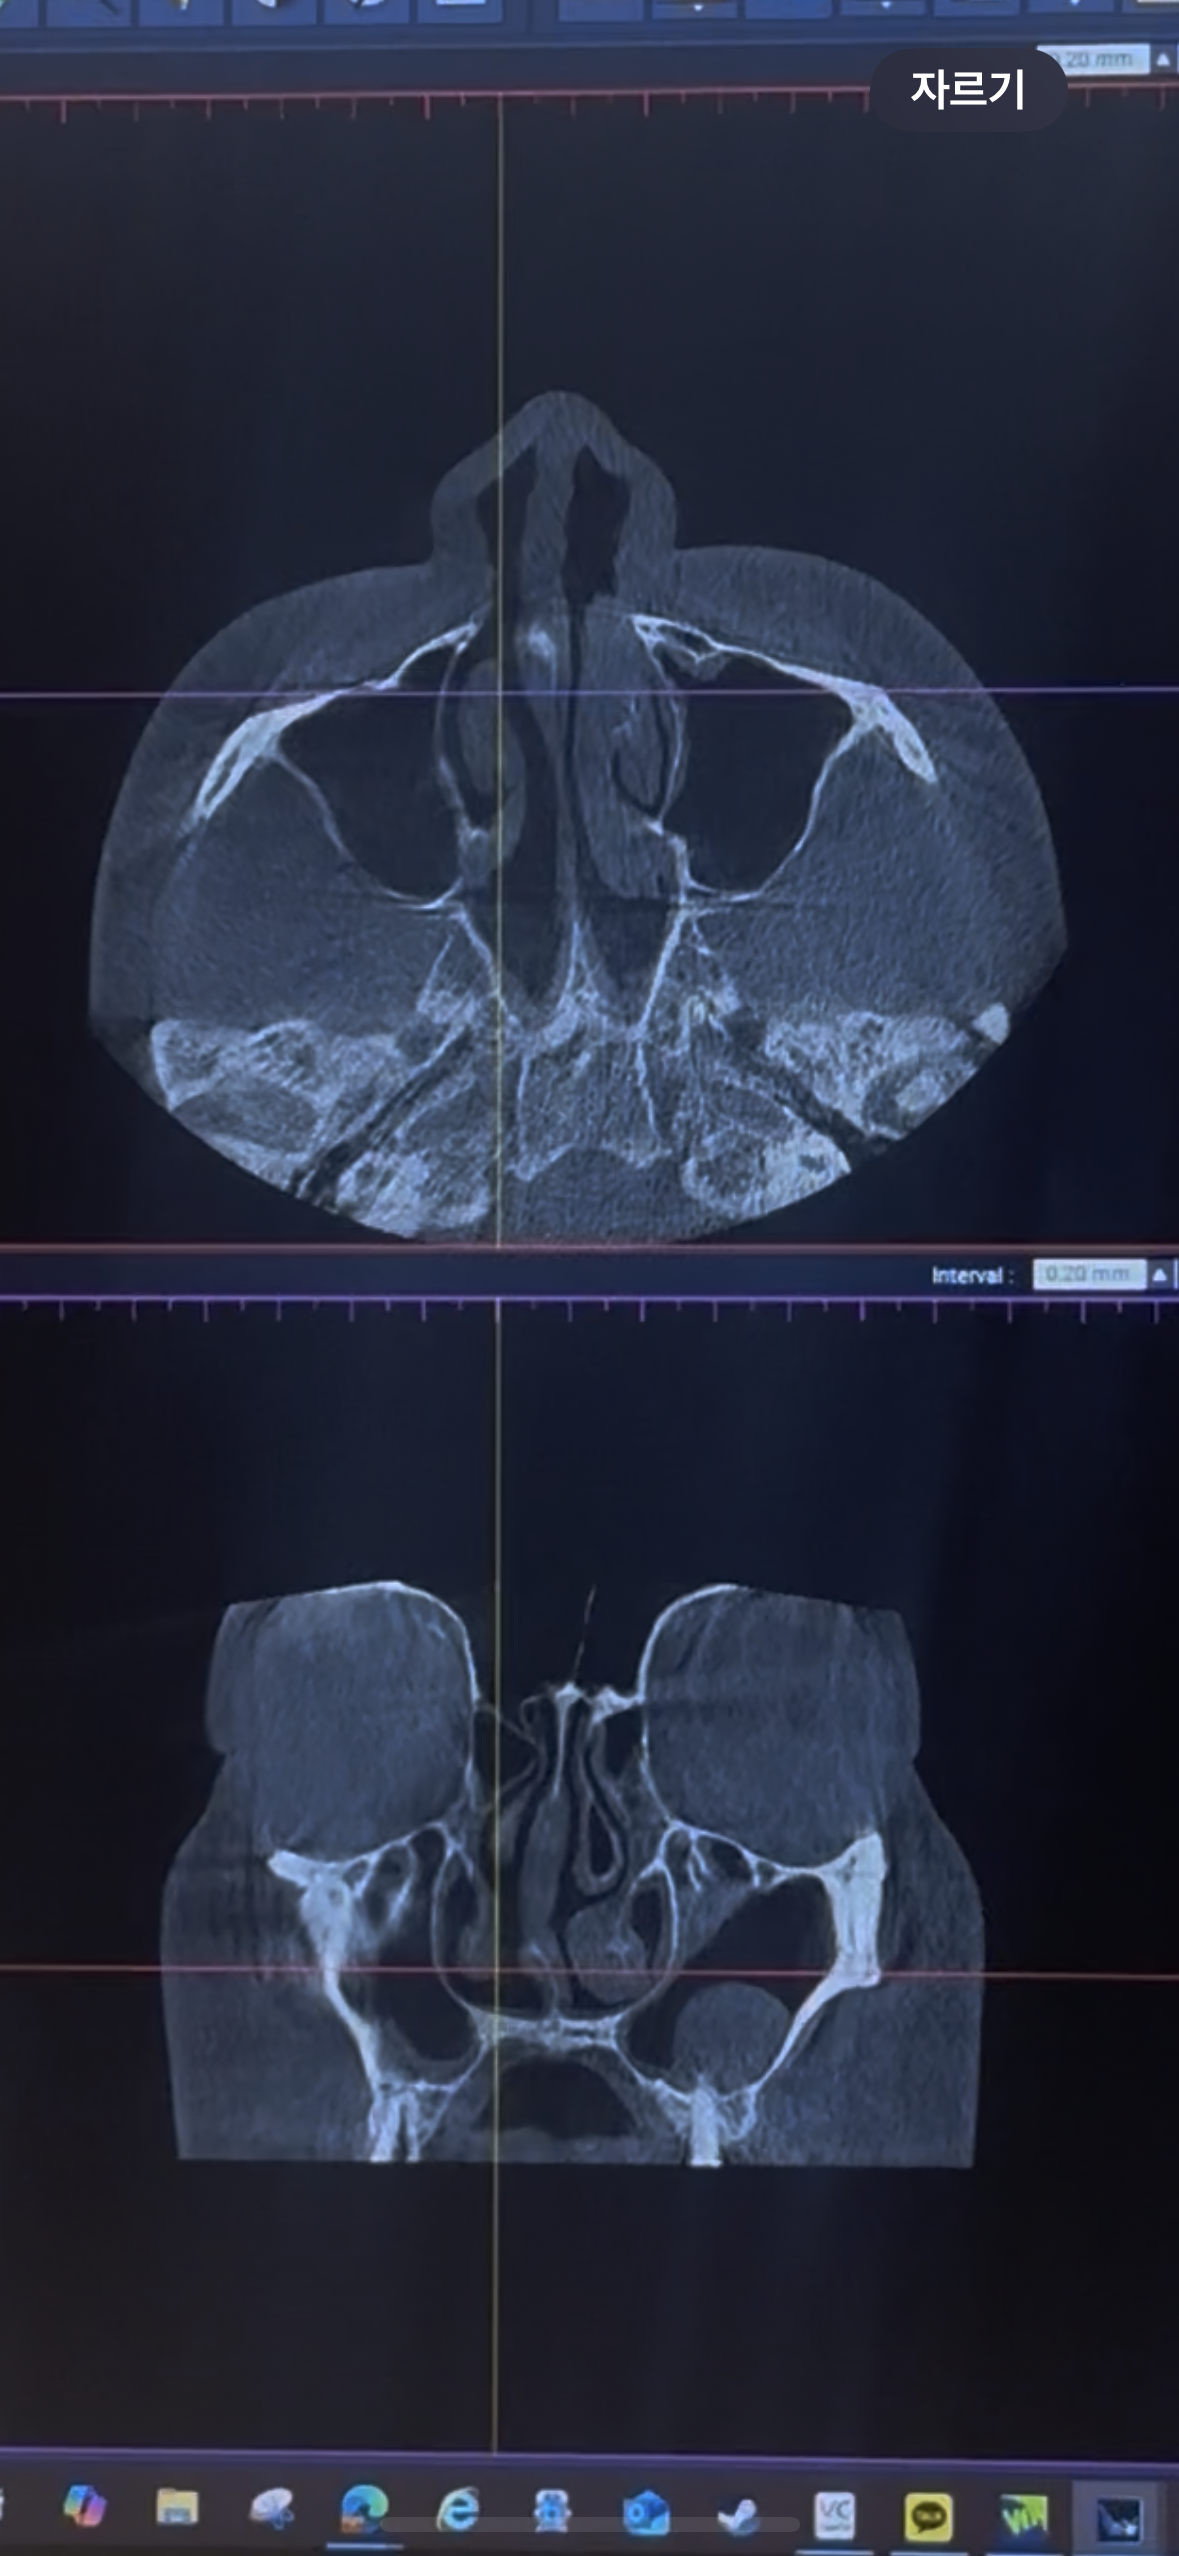

기능1종 비중격만곡증 수술과 코끝은 비중격 + 귀연골로 올해 2월에 수술했어 숨쉬기 불편하고 코 한쪽이 이물감이 심하고 코끝이 휘어서 경과 보러가면서 ct를 찍었는데 ct보여주면서 설명은 안해주시고 ct 원장님이 보고오셨다면서 이상없다고 잘됐다고만 하고 끝났어 근데 나는 너무 불편해 ㅜ

근데 ct 폰으로 찍어놨는데 혹시 ct볼 수 있는 사람중 내 ct봐줄수있어? 실장님께 연락은 넣었는데 확인해주고 연락준다고하셨는데 아직까지 연락이 없어서 그전에 너무 뷸안해서 글 올려 ㅜ